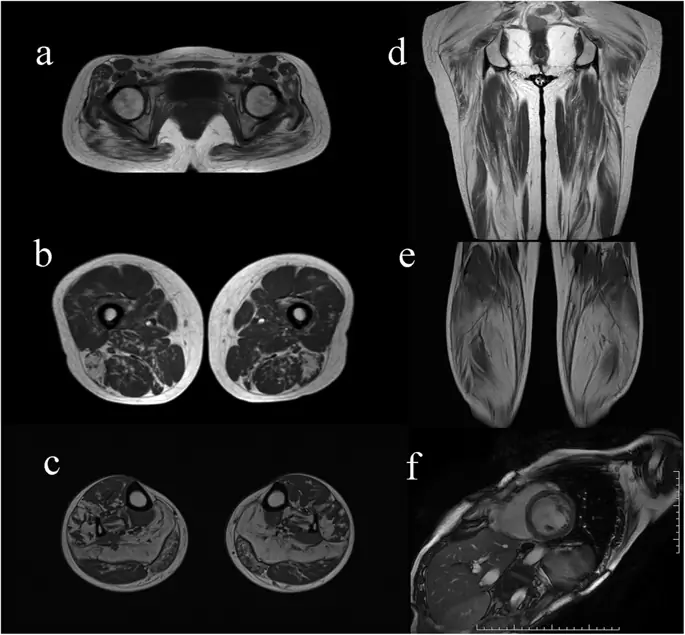

Двадцать один пациент перенес МРТ на бедра и 16 - на телятах. Асимметричная жировая инфильтрация наблюдалась у пяти пациентов, которая была заметна на правой конечности двух пациентов и на левой конечности трех пациентов. Жирная инфильтрация появилась на бедрах 19/21 (90, 5%) пациентов. По данным МРТ, длинная головка двуглавой мышцы бедра, полимембраноз и большая мозговая мышца были тремя наиболее сильно пораженными мышцами. Прямоугольные мышцы бедра, грацилис и сарториус были тремя худшими мышцами. Жировая инфильтрация появилась в голенях у 16/16 (100%) пациентов. Верхними двумя сильно инфильтрированными мышцами были подошва и медиальная головка икроножной мышцы. Верхними двумя наименее инфильтрированными мышцами были передняя большеберцовая кость и задняя большеберцовая кость (рис. 2, рис. 3, дополнительный файл 1).

фигура 2

МРТ голени и мышцы сердца у пациентов с NLSDM. МРТ показала диффузную жировую инфильтрацию, преимущественно с участием большой ягодичной мышцы на уровне таза. b, d Длинная головка двуглавой мышцы бедра, полимембраноз и большой аддуктор поражены от умеренной до тяжелой степени. Прямая кишка бедренная кость, gracilis и sartorius были относительно сохранены. c, e Селезенок и медиальная головка икроножной мышцы были сильно поражены. Передний и задний голени были относительно сохранены. (f) МРТ сердца показала дилатационную кардиомиопатию

Изображение в полном размере

Мы обнаружили признаки тяжелой жировой инфильтрации в длинной головке двуглавой мышцы бедра, длинном аддукторе, полумембранозе, большой ягодичной мышце, подошве и медиальной головке икроножной мышцы у наших пациентов с NLSDM, некоторые из которых были ранее описаны в случаях (3, 4, 5, 8, а. Мышечный нерв. 2015; 51: 922-7. "Href =" / Articles / 10.1186 / s13023-019-1209-z # ref-CR12 "> 12, 15, 16, 17, 19, 22). Так как липидные капли в основном появились в виде 1 волокон, мышечная избирательность при NLSDM может быть связана с поддержанием стоячей позы от задних мышц, которые содержат высокую долю медленных подергивающих оксидных волокон типа 1. Мы также обнаружили, что икроножные мышцы были вовлечены более серьезно и диффузно по сравнению с мышцами бедра, даже при проксимальной миопатии, предполагая, что МРТ нижних конечностей более ценна для диагностики NLSDM на ранней стадии. Асимметричная жировая инфильтрация ног наблюдалась только в шести случаях, что указывает на то, что мышечная асимметрия в основном затрагивала верхние конечности и имела тенденцию становиться однородной с прогрессированием заболевания. Интересно, что паттерн мышечного вовлечения в нашей серии был сходным как в типичных, так и в легких случаях фенотипа, а также при бессимптомной гиперкемии (8). Таким образом, паттерн мышечного МРТ был чувствительным индикатором для диагностики NLSDM. Селективное вовлечение задних мышц Это также частично наблюдается при других заболеваниях мышц, включая десминопатию, фасциокапулохимеральную мышечную дистрофию, кальпаинопатию или дисферлинопатию (29, 30), хотя относительная экономия полудендиноза, сарториуса и грацили и отсутствие мышечной гипертрофии полезны для дифференциальной диагностики (31).). За исключением воспалительных миопатий, мышечный отек также наблюдается при метаболической миопатии, некоторых типах мышечной дистрофии и нейрогенных расстройствах. В отличие от замещения жира, отек мышц в нашей серии не показал четкого и последовательного распределения и может происходить вторично по отношению к недостаточности мышечной энергии при NLSDM. Тем не менее, необходимы дальнейшие исследования, чтобы оценить связь мышечного отека с активностью заболевания.